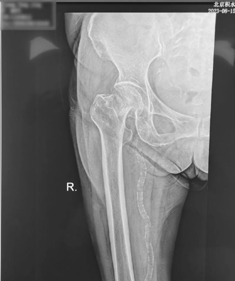

8月14日,67岁的梁阿姨在买菜途中不小心摔倒,右髋疼痛,无法站立,被家人紧急送到附近医院,拍片显示右侧股骨粗隆间骨折,当地医生告知这是老年骨质疏松骨折,需要手术。听说北京积水潭医院有老年髋部骨折的绿色通道,梁阿姨当即就被转诊到北京积水潭医院新街口院区创伤骨科急诊。经过急诊快速通道,完成术前检查和麻醉评估,准备手术,但术前检查显示梁阿姨血压、血糖较高,同时存在肾功能不全、低氧血症情况。这可把梁阿姨一家急坏了。主管医师立即请心内科、内分泌科、肾内科及呼吸内科会诊。在专家团队的精心治疗下,梁阿姨的各项指标均达到手术标准,于7天后完成了人工股骨头置换术手术。术后第一天,梁阿姨能够坐立在床边,第二天梁阿姨能够借助助行器短距离步行,第三天梁阿姨出院。